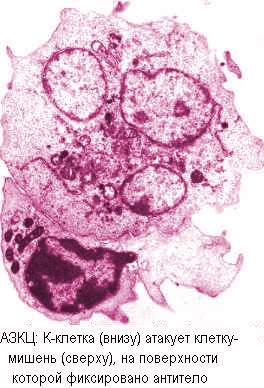

· Цитотоксические антитела способны опосредовать прикрепление больших гранулярных лимфоцитов и других К-клеток - к клеткам-мишеням и вызывать повреждение путем антителозависимой клеточной цитотоксичности (АЗКЦ). При АЗКЦ антитела первично специфически связываются Fab-фрагментами с соответствующими детерминантами клеточной мембраны; это специфическая стадия. Во второй - неспецифической стадии клетки, несущие рецепторы к Fc-фрагменту антител (макрофаги, лимфоциты, моноциты, гранулоциты) активируются, причем макрофаги и К-клетки, а при противоопухолевых реакциях - и NK-клетки (нуль-клетки - лимфоциты, которые проявляют активность в АЗКЦ, но не несут маркеров, типичных для Т- и В-лимфоцитов) способны оказать цитотоксический эффект на клетку, помеченную антителами, с помощью перфориноподобного механизма, не поглощая мишень. Механизм АЗКЦ может иметь значение при ряде аутоиммунных заболеваний (хронический прогрессирующий гепатит, язвенный колит, тироидит, и пр.), антиопухолевом иммунитете, паразитарных и вирусных заболеваниях, а также реакциях отторжения трансплантата.